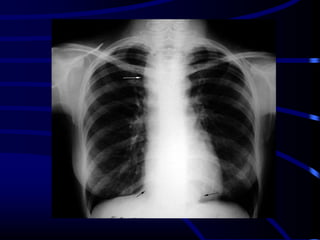

Atelectasis Right Lung

Homogenous density right hemithorax

Mediastinal shift to right

Right hemithorax smaller

Right heart and diaphragmatic silhouette are not identifiable